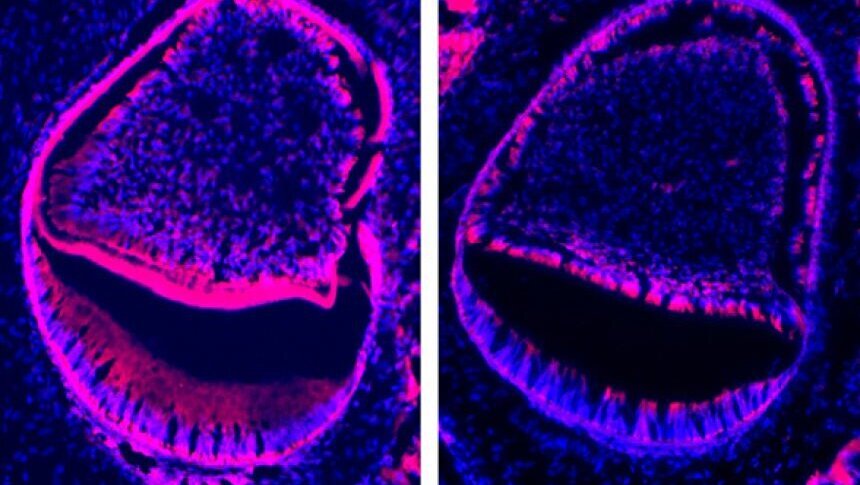

Les chercheurs ont utilisé un modèle de souris de laboratoire, pour cette étude dans laquelle ce gène a été «assommé» et sa protéine absente. Ces souris manquent des systèmes de base biologiques et ne peuvent vivre après la naissance, mais elles permettent aux scientifiques d'étudier ce qui est là, et ce qui manque.

Dans ce cas, les souris avaient des dents rudimentaires, prêtes à pousser, mais il leur manquait une bonne couche d'émail et n'auraient jamais été fonctionnelles.